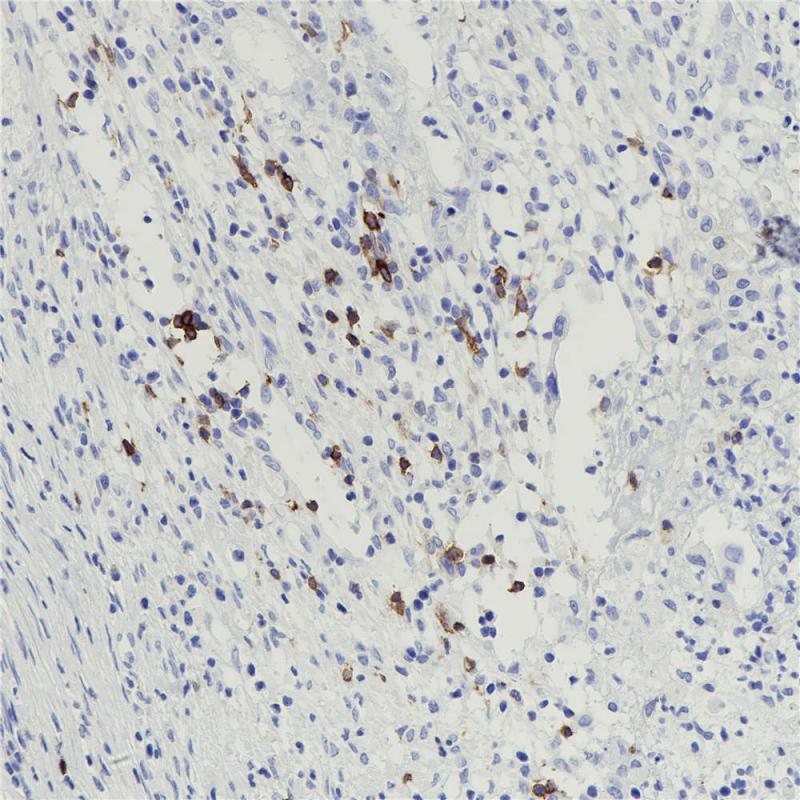

Olig2

BP6167